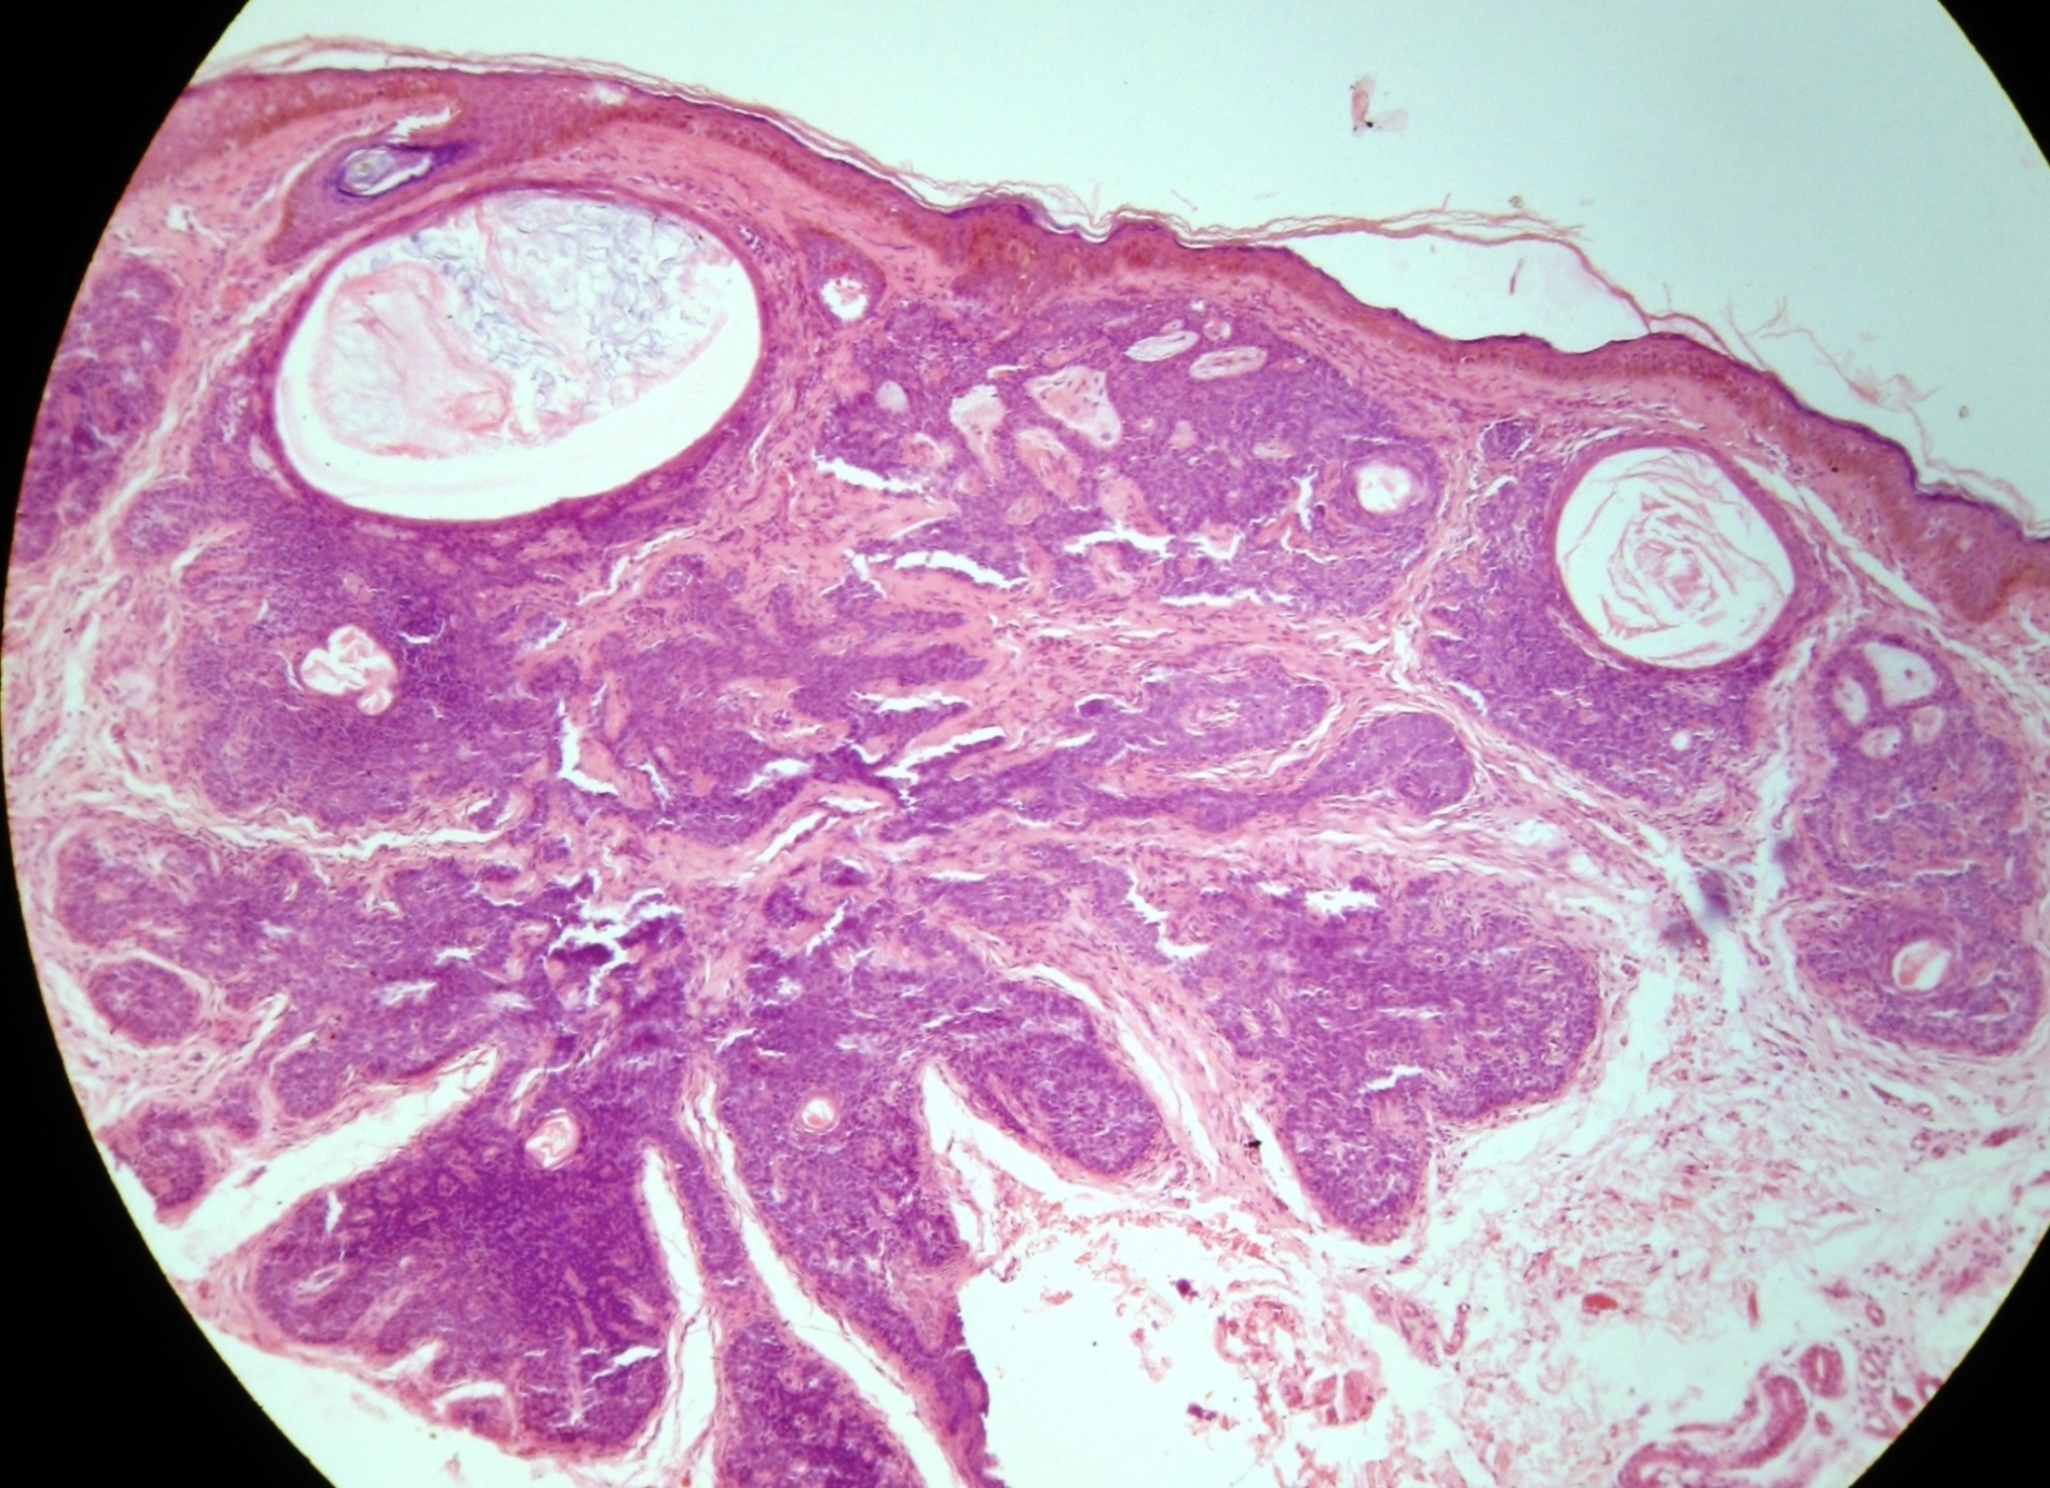

Fig 2: Histopathology showing lobules of small, dark basaloid cells, with peripheral palisading surrounding a central area of eosinophilic amorphous material (H&E X 40).